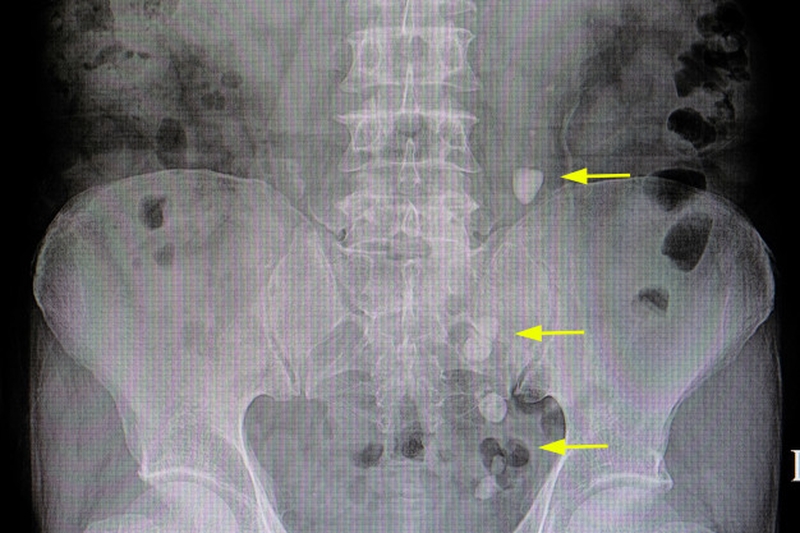

Ở người mắc bệnh thận mạn, chế độ ăn nhiều muối có thể làm bệnh tiến triển nhanh hơn do làm tăng huyết áp và tăng gánh nặng cho thận. Ngược lại, giảm lượng muối giúp kiểm soát huyết áp và hỗ trợ bảo vệ chức năng thận. Ngoài ra, ăn nhiều muối còn có thể làm tăng nguy cơ sỏi thận do tăng thải calci qua nước tiểu.